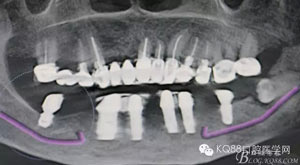

圖2.術前的CBCT影像檢查:38牙根尖靠近下頜神經管。該CBCT是未帶烤瓷冠之前拍的。